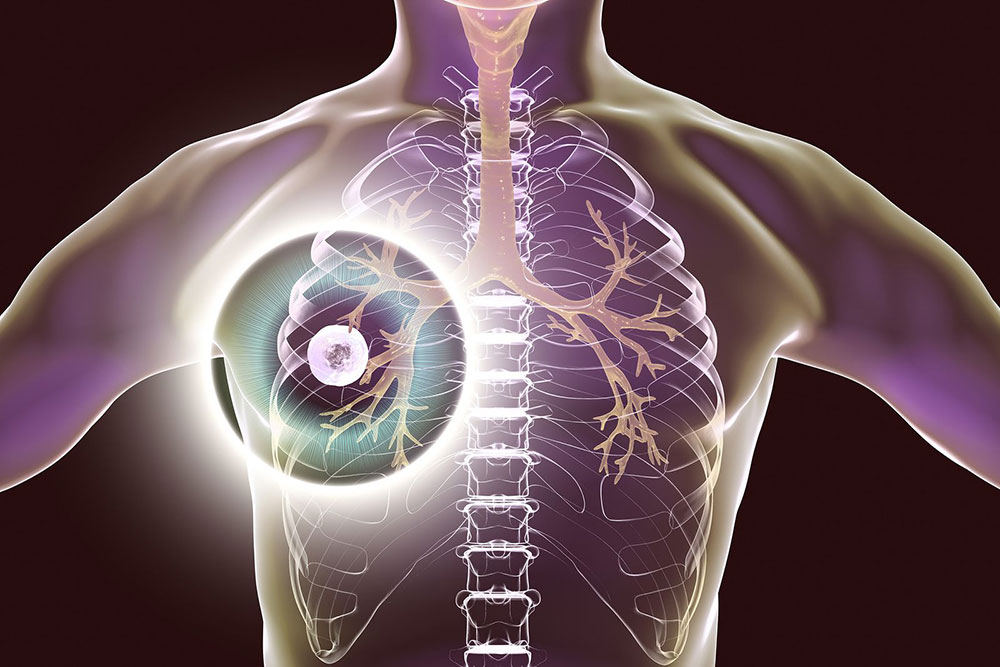

Read moreLa tuberculosis, una enfermedad bacteriana que afecta principalmente los pulmones y se transmite por vía aérea, mostró un crecimiento sostenido ...

Read moreLa tuberculosis (TB) es una de las enfermedades más antiguas que afectan a la humanidad. A pesar de los avances ...